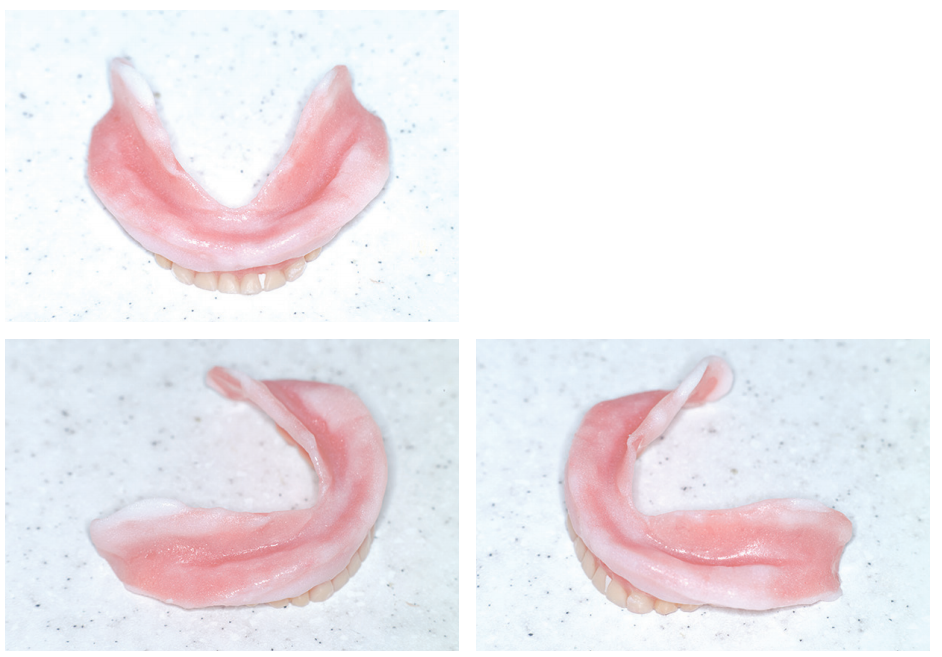

2) 하악 완성 틀니 2차 기능인상

완성 틀니에서 tissue conditioner를 이용하여 retromylohyoid fossa 하방으로 확장을 위해 2차 기능인상을 실시하였다.

식사 후 빼서 세척할 때 외에는 잠자는 시간에도 틀니를 끼고 생활하도록 당부하였다. 3일 후에 내원하였다.

Mylohyoid ridge 하방으로 tissue conditioner가 두툼하게 자리하고 있다. 더 연장을 할 목적으로 tissue conditioner를 첨가하였다.

이때는 tissue conditioner를 좀더 묽게 혼합하여 연장을 시행한다. 2~3분 정도 형태를 만든 후 어느 정도 굳으면 입안에 넣어 물고 있도록 한다.

다시 3일 후에 내원하였다. 하악 틀니 유지력이 개선되었다.

3) Top coat coating

모든 tissue conditioner 계통 재료는 표면이 다공성이어서 거칠다. 이 상태로 relining 하면 틀니 내면에 음식물 침착과 착색이 쉽게 일어날 뿐 아니라 유지력 또한 저하된다.

Top coat를 경화된 tissue conditioner 표면에 두세 번 바른 후 건조시킨다. 치과기공소에 relining을 하도록 의뢰하였다.